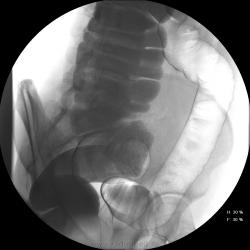

Девушка, 27 лет, жалуется на периодические боли в правой подвздошной области, области паха справа. Во время этого идет нарушение стула - то слабит, то несколько дней не может ходить в туалет, вздутие кишечника. Жалобы несколько лет . Обследованна кем только можно. Хирург посоветовал ирригоскопию. Работа достаточно нервная. До первого случая данных проблем , за неделю, проходила сан лечение в пансионате ( для поднятия общего иммунитета - так говорит), был курс клизм с травами - сама думает, что это не связанно.

При таких симптомах ищи "бабьи дела", может быть хр. аппедицит. Необходимо определиться с характером и продолжительностью болей. Наиболее вероятнно - недостаточность функции Баугиневой заслонки. При указании или подозрении на эту патологию меняется методика обследования. Ваши снимки расположены хаотично, а не по мере заполнения кишечника. При подзрении на недостаточность функции Баугиневой заслонки, по рекомедации Шнигера, заполняется толстая кишка до печёночного угла, а далше только с помощью глубокой пальпации. Если в этом случае удаётся провести контраст в тонкую кишку или при опорожнеии кишечника контраст попадает в тонкую - пиши недостаточность Баугиневой заслонки.

А, чем вызвана неоднородность контрастирования слепой и частично восходящего отдела?

Тугого контрастирования слепой не достигнуто. Должны быть причины.

Слепая кишка в конце исследования, несмотря на её содержимое, заполнилась прилично. А вот гаустрация сигмовидной кишки не сглажена?